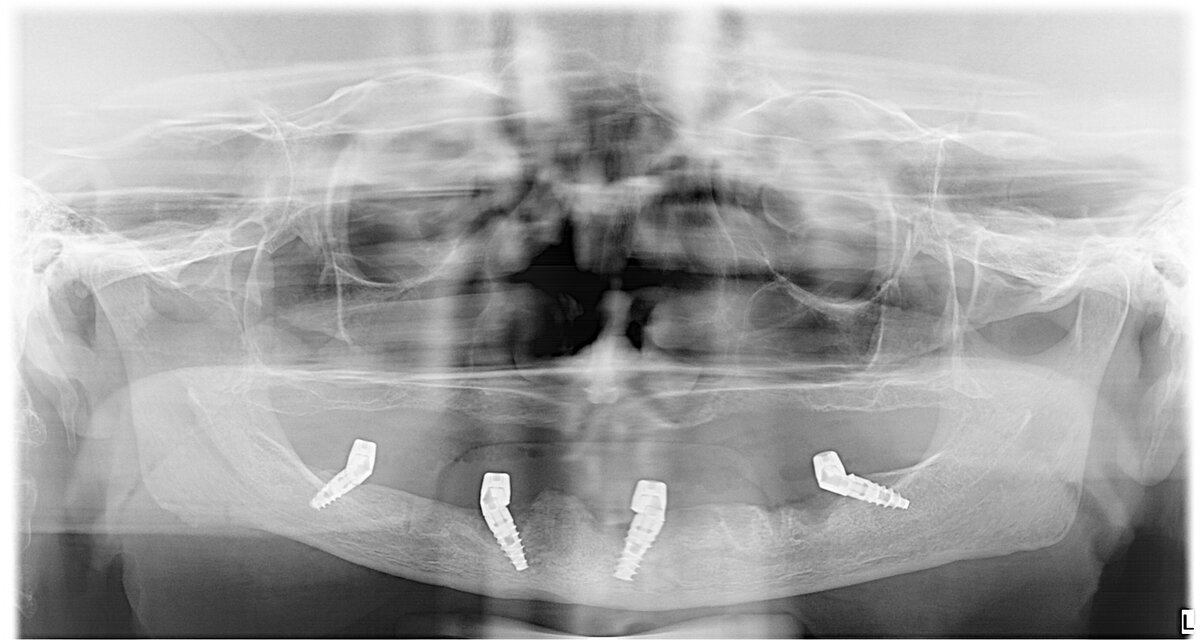

Есть выход. Это имплантация, и изготовление полного зубного ряда за 24 часа. Да, сегодня это осуществимо. Даже если есть недостаточность кости и слизистой полости рта , покрывающей кости челюстей. В данном клиническом случае имплантаты установлены в нестандартных позициях и с большим наклоном из-за недостаточности кости. Удалость собрать зубные ряды за 24 часа. И эта милая женщина счастлива. Есть уже огонёк в глазах и желание жить и радоваться жизни. Посмотрите как это здорово получилось.